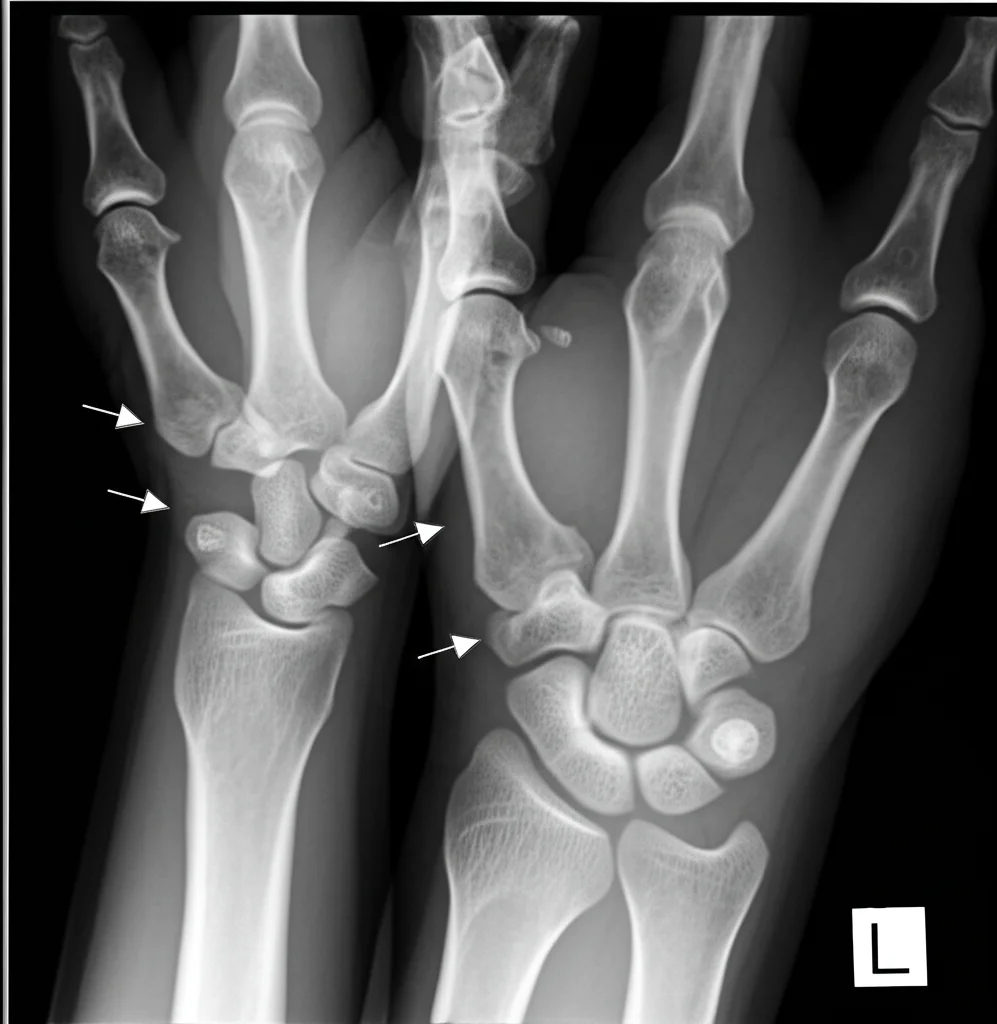

Ma le sorprese non finiscono qui. Ricordate le cisti ossee tipiche della NHD? Abbiamo documentato il caso di una donna di 34 anni, portatrice di una sola copia della delezione TYROBP, che presentava le classiche cisti ossee dolorose ai polsi e alle caviglie, molto simili a quelle viste nei pazienti NHD, ma *senza* alcun sintomo cognitivo o alterazione cerebrale rilevabile alla risonanza magnetica. Il suo fratello, invece, con entrambe le copie delete e diagnosi di NHD, mostrava lesioni ossee molto più estese e gravi, oltre a evidenti segni di atrofia cerebrale e calcificazioni. Questo caso è affascinante perché dimostra che anche una riduzione parziale della funzione di TYROBP/DAP12 può manifestarsi a livello osseo, suggerendo un effetto “dose-dipendente” del gene. Abbiamo anche studiato un’altra portatrice monoallelica, una donna di 75 anni con idrocefalo normoteso e marcatori di patologia Alzheimer nel liquor e nella biopsia cerebrale, ma in questo singolo caso non abbiamo visto differenze nette nella patologia amiloide o nella risposta microgliale rispetto ai non portatori. Serviranno più campioni per capire meglio questo aspetto.